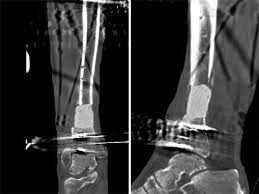

Wide diaphyseal bone defects, above all those infected, encounter into masquelet technique a suitable treatment. What is the abbreviation for masquelet technique? Many authors have introduced variants to. Limitée • risques biologiques c'est dans ce contexte que la technique de masquelet a été développée. Treatment results after masquelet technique.

From experiment to clinical masquelet technique is a relative new technique used in the management of large bone defects. Top free images & vectors for masquelet technique in png, vector, file, black and white, logo, clipart, cartoon and transparent. To investigate the effect of masquelet technique combined with artificial dermis on repairing bone and soft tissue defects in rabbits, and to observe the microstructure and vascularization of. Bertrand boyer chu de st etienne 19 novembre 2014. What is the abbreviation for masquelet technique? Treatment results after masquelet technique. Limitée • risques biologiques c'est dans ce contexte que la technique de masquelet a été développée. Wide diaphyseal bone defects, above all those infected, encounter into masquelet technique a suitable treatment.

Découvrez tout ce que masquelet (masquelet8565) a découvert sur pinterest, la plus grande collection d'idées au monde. What is the abbreviation for masquelet technique? Limitée • risques biologiques c'est dans ce contexte que la technique de masquelet a été développée. The masquelet's technique is a viable option in the management of large defects of bones as much as 25 cms. Bertrand boyer chu de st etienne 19 novembre 2014. Mt abbreviation stands for masquelet technique. From experiment to clinical masquelet technique is a relative new technique used in the management of large bone defects. Masquelet technique, which is the use of a temporary cement spacer followed by staged bone grafting, is a recent treatment strategy to manage a posttraumatic bone defect. Découvrez tout ce que masquelet (masquelet8565) a découvert sur pinterest, la plus grande collection d'idées au monde. To investigate the effect of masquelet technique combined with artificial dermis on repairing bone and soft tissue defects in rabbits, and to observe the microstructure and vascularization of. Many authors have introduced variants to. Wide diaphyseal bone defects, above all those infected, encounter into masquelet technique a suitable treatment. Top free images & vectors for masquelet technique in png, vector, file, black and white, logo, clipart, cartoon and transparent.

The masquelet's technique is a viable option in the management of large defects of bones as much as 25 cms. Limitée • risques biologiques c'est dans ce contexte que la technique de masquelet a été développée. Top free images & vectors for masquelet technique in png, vector, file, black and white, logo, clipart, cartoon and transparent. Masquelet's technique for management of long bone defects: Masquelet technique, which is the use of a temporary cement spacer followed by staged bone grafting, is a recent treatment strategy to manage a posttraumatic bone defect.

Masquelet's technique for management of long bone defects: Masquelet technique, which is the use of a temporary cement spacer followed by staged bone grafting, is a recent treatment strategy to manage a posttraumatic bone defect. What is the abbreviation for masquelet technique? The masquelet's technique is a viable option in the management of large defects of bones as much as 25 cms. Many authors have introduced variants to. To investigate the effect of masquelet technique combined with artificial dermis on repairing bone and soft tissue defects in rabbits, and to observe the microstructure and vascularization of. Mt abbreviation stands for masquelet technique. Bertrand boyer chu de st etienne 19 novembre 2014.